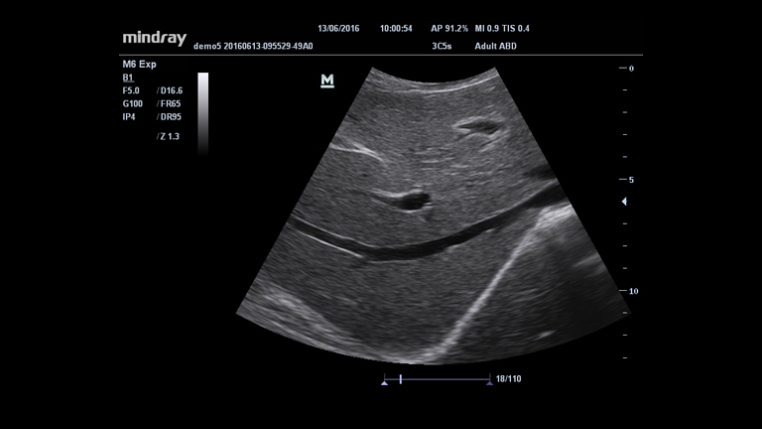

System diagnostyki USG

Specjaliści kliniczni przebyli długą i trudną drogę, aby uzyskać możliwość stosowania diagnostyki obrazowej o wysokim standardzie przy łóżku pacjenta poddawanego intensywnej opiece medycznej. Dotychczas wybór wielkości i wydajności aparatów USG był ograniczony. Mając na względzie dostępność opieki zdrowotnej, Firma Mindray wprowadziła nowy aparat M6, idealnie łączący w sobie możliwości i rozmiar potrzebne do niezawodnego diagnozowania pacjenta przy łóżku.